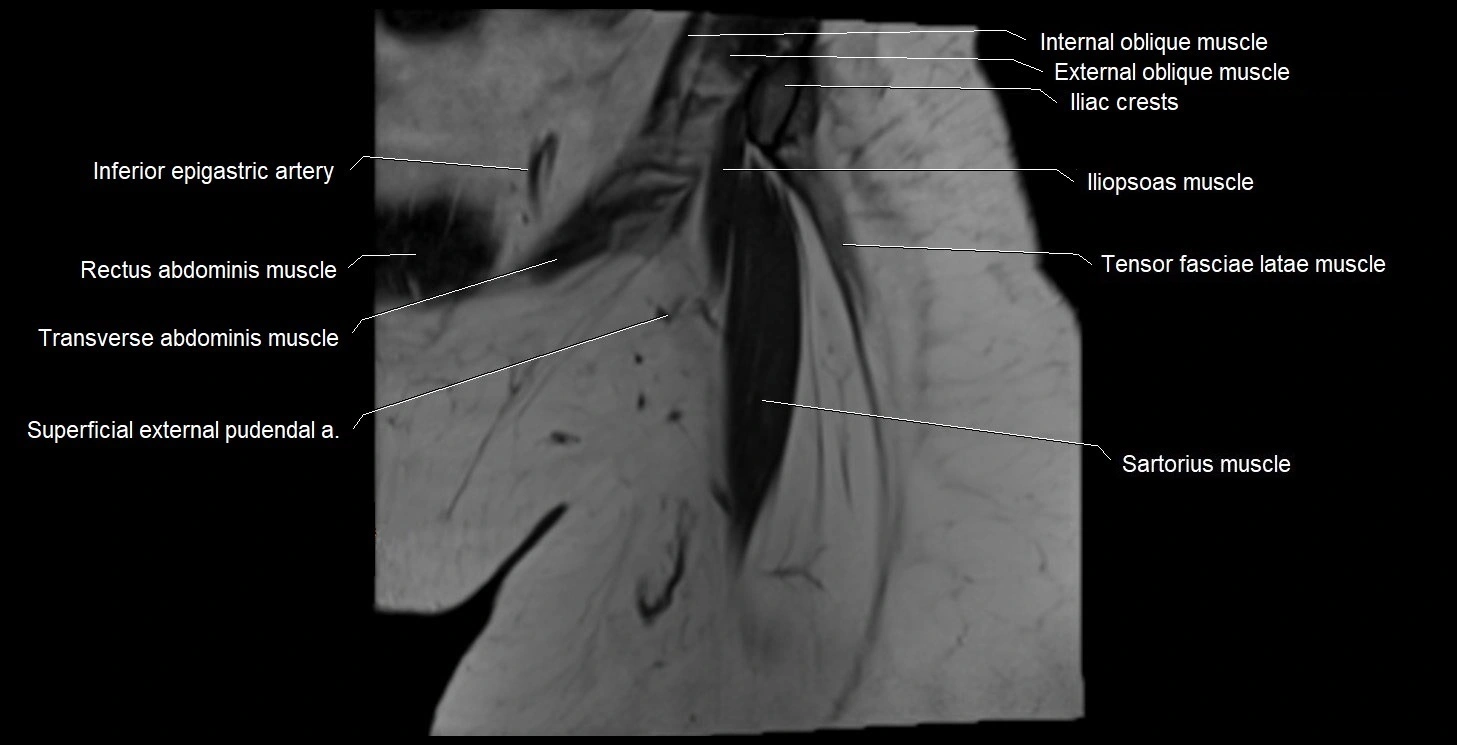

- Iliopsoas muscle

- Inferior epigastric artery

- Sartorius muscle

- Tensor fasciae latae muscle